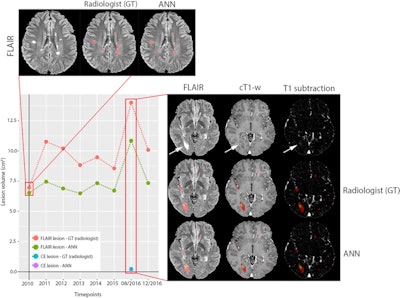

Example of a longitudinal comparison between radiologist-segmented MS lesions and ANN-segmented MS lesions, showing a good overlap between the two volumes. At the MRI follow-up of August 2016, the patient showed a large new lesion with a faint central contrast enhancement (both indicated by the arrows in FLAIR and T1 after contrast, respectively), which the ANN correctly detected. The lesion then regressed under therapy and was unremarkable at the next follow-up. While underestimating the volumetric size of the lesions, the ANN consistently reproduced the volumetric trend of the follow-up for this patient. Image courtesy of Drs. Gianluca Brugnara and Philipp Kickingereder and European Radiology.